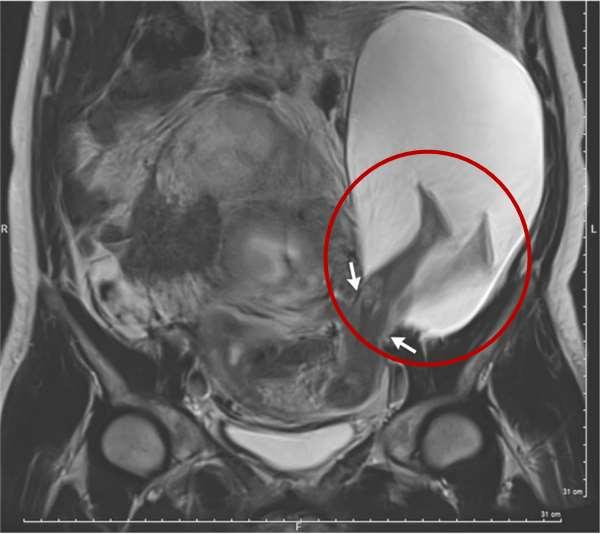

從這張核磁共振的影像中,可以看到這名生命力強烈的嬰兒,踹破母親的子宮,將腳伸出子宮外踢到其他器官,離奇的畫面就連醫生也被嚇壞了。

不久之前,當法國的婦產科醫生Pierre-Emmanuel Bouet替懷孕22週的孕婦產檢時,赫然發現到胎兒並沒有好好地待在子宮內生長,反而是兩腳伸直的穿出子宮外,罕見畫面讓醫生直呼:「從來沒看過!」就連醫學文獻上也僅有26起案例。

據悉,該名孕婦之所以會有這麼嚴重的子宮壁撕裂,起因在於先前的五次剖腹生產,雖然剖腹留下的疤痕會變厚,不過周圍的子宮壁會變得比以往脆弱,然而再懷孕後的壓力容易將子宮壁撐得更薄,於是在胎兒強勁的胎動後,往往會造成撕裂的狀況發生,所以沒有意外的,包著羊膜的寶寶的腳也就隨著滑出子宮的缺口。